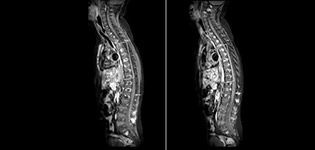

À l’hôpital pour enfants de Phoenix, l’imagerie de susceptibilité pondérée haute résolution avec SWIp est désormais courante pour examiner les traumatismes crâniens. L’imagerie de perfusion rapide et sans contraste avec pCASL est utilisée chez tous les patients souffrant d’accidents vasculaires cérébraux aigus ou d’anomalies telles que les AVC graves. L’excellente suppression de graisse de la TSE mDIXON est devenue la norme de l’hôpital pour la suppression de graisse dans le rachis et les membres, l’examen des lésions des tissus mous du visage et du cou et les anomalies contrastées, qui sont principalement visibles avec la suppression de graisse.

La TSE mDIXON Philips est une technique DIXON à deux points qui sépare les signaux d’eau et de graisse pour une imagerie sans graisse rapide, même dans le domaine complexe de la neuroanatomie. “La TSE mDIXON est l’une des améliorations les plus importantes des séquences d’imagerie que nous utilisions jusqu’alors au PCH”, admet le Dr Miller. “Son acquisition multi-paramétrique nous permet d’obtenir dans la même séquence des images avec suppression de graisse et les images T2 équivalentes sans suppression de graisse. En outre, les anciennes méthodes de suppression de graisse pouvaient être corrompues artificiellement par une anatomie inhabituelle du patient ou par une mauvaise application de l’opérateur. Avec mDIXON, nous disposons désormais d’une méthode efficace et fiable pour supprimer la graisse.” La saturation de la graisse a toujours été difficile aux extrémités du champ d’acquisition, en particulier dans l’imagerie du rachis total et dans les zones anatomiques difficiles, comme les régions inférieures du cou. “Toutefois, grâce aux capacités uniques de suppression de graisse du mDIXON, ces difficultés ne sont plus valables” affirme le Dr Miller. “Nous obtenons quotidiennement une suppression de graisse homogène dans presque toutes les conditions. Cela nous a également mené à un meilleur rendement puisque nous n’avons plus à répéter les séquences à cause des défaillances techniques.”

“La TSE mDIXON a renforcé la fiabilité de nos diagnostics en nous permettant de garder ou d’écarter les anomalies pour lesquelles la suppression de graisse est essentielle au diagnostic, comme les maladies métastatiques ou les anomalies osseuses.”

“La TSE mDIXON est la technique la plus utile chez les patients atteints de lésions ou d’anomalies des tissus mous, par exemple du visage et du cou, et chez les patients victimes d’anomalies de contraste principalement visibles avec la suppression de graisse”, indique le Dr Miller. “Toutes nos imageries du rachis contiennent désormais des images T2 mDIXON avec eau uniquement, ce qui nous permet d’identifier les pathologies potentiellement obscurcies par l’imagerie sans suppression de graisse comme les lésions osseuses. Par ailleurs, il n’est pas nécessaire d’acquérir des images TSE T2 standard supplémentaires car les images mDIXON en phase sont équivalentes aux images TSE T2 standard.”